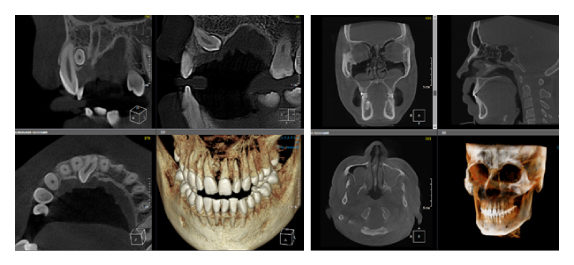

4. Универсальность программы-просмотровщика

Ещё одна актуальная проблема в современной стоматологии — это огромное количество разных программ просмотровщиков конусно-лучевой компьютерной томографии. Каждый производитель этого ПО старается сделать что-то уникальное, и для конечного доктора это порой усложняет диагностику. Вы привыкли работать в одной программе, а тут уже пришел пациент с КЛКТ исследованием в совершенно незнакомом софте. У меня даже существует отдельный курс по разбору разных программ, чтобы врач всегда мог сориентироваться и провести консультацию. Но если вы решили купить собственный дентальный томограф, то здесь совет брать программу, которая технически удовлетворит все ваши запросы. Стоит помнить о том, что если вы будете проводить исследования не только для нужд своей клиники, но и сторонним, то эта программа не должна быть обрезанной по функционалу, являться простой, русифицированной, а также знакомой и понятной многим. От себя хочу добавить, что советую обращать внимание на возможность использования различных фильтров резкости изображения, изменения толщины среза, возможность построения произвольных кросс-секций на панорамном реформате, а также большой базы имплантатов (рис. 5), и чтобы всё это было доступно не только в лицензии, но и во viewer (просмотровщике, который получает конечный врач).

Рис. 5. Пример программы OnDemand3D. Панорамный реформат с повышенным фильтром резкости, произвольной кросс-секцией, установленным виртуальным имплантатом.